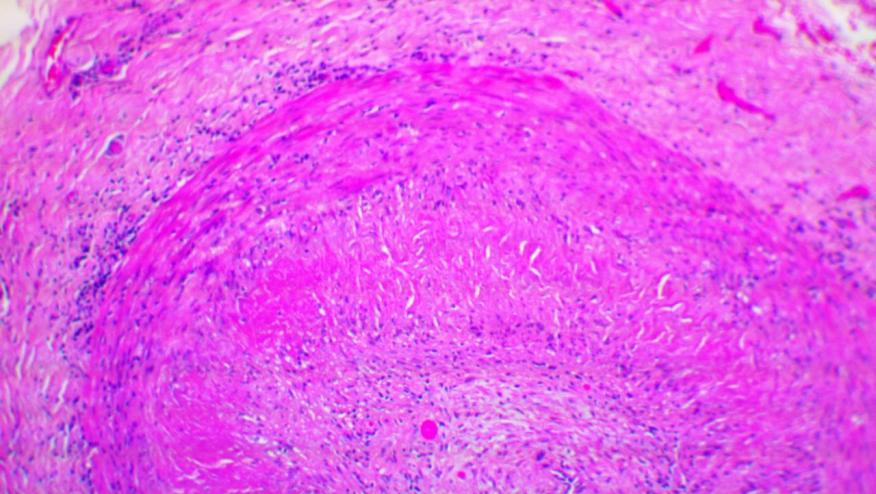

Varicella-zoster virus infection was studied in temporal artery biopsies from those suspected of having giant cell arteritis. VZV antigen was found in 61/82 (74%) GCA-positive temporal arteries (TA) compared with 1/13 (8%) normal TAs (p 0.0001, with RR=9.67, 95% CI ;1.46, 63.69). Most GCA-positive TAs contained viral antigen in skip areas. VZV antigen was present mostly in adventitia, followed by media and intima. VZV antigen was found in 12/32 (38%) skeletal muscles adjacent to VZV antigen-positive TAs. Antiviral treatment may confer additional benefit to patients with GCA treated with corticosteroids, although the optimal antiviral regimen remains to be determined.